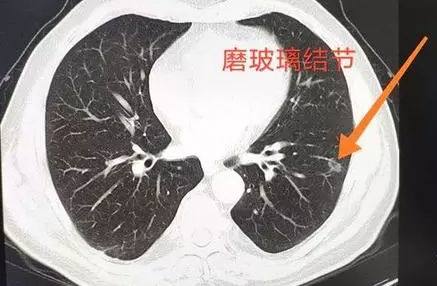

患者如果患有肺部磨玻璃一样的结节,如何进行治疗,则应该及时的到医院进行详细的相关检查,明确导致肺部的磨玻璃结节的具体原因之后,然后则应该在医生的指导下,依据检查结果来选择如何进行治疗。

肺部磨玻璃结节一般治疗上分为两种情况,第一种治疗是需要进行保守治疗。这种磨玻璃结节,如果考虑炎症或者是结核引起的,可以应用一些抗炎药物或者是应用联合的抗结核药进行治疗,动态观察肺部磨玻璃结节的变化情况。如果药物治疗效果比较理想,一般定期复查就可以了。

而对于毛玻璃一样的一些肺部结节,如果比较大或者是形态并不是特别规则,那么针对于这种情况,应该考虑第二种方案就是进行穿刺取病理,必要时也可以做一些开胸探查手术,切除这个肺结节,然后做病理进一步的评估,如果考虑癌性可能性比较大,就要直接做肺癌的根治性手术,这样效果会比较理想。经过手术和其他治疗措施,大多数疾病都可以治愈。